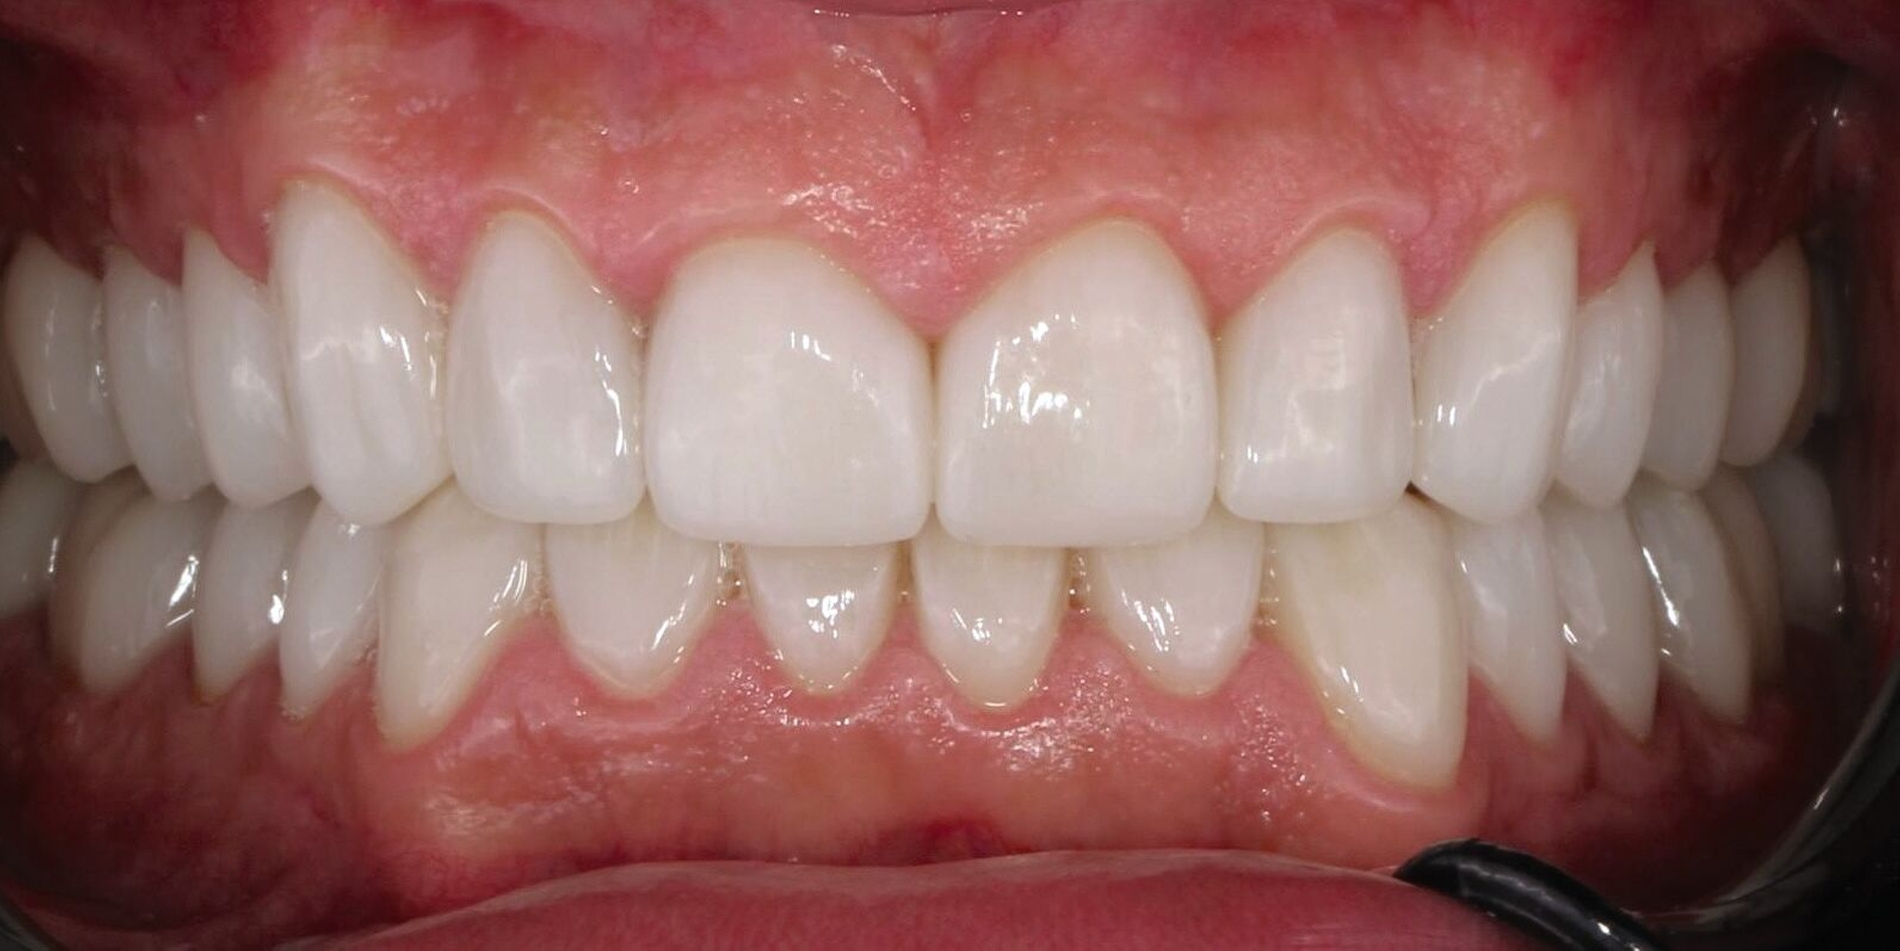

Zu Beginn wurden mit Alginat Abformungen der Ausgangslage genommen. Anhand der Situationsmodelle konnten mithilfe einer Modellanalyse nach dem Udo-Plaster-Protokoll [Plaster und Köttgen, 2020] Rückschlüsse auf einen vertikalen Höhenverlust von etwa 3 - 4 mm gezogen werden. Für die Registrierung der neuen Höhe wurde der Patient mit einer temporären Einweg-Schiene (Aqualizer®, MediPlus GmbH, Unterleinleiter) deprogrammiert. Anschließend wurde am stehenden Patienten ein Bis-Acrylat-basierter Frontzahn-Jig (LuxaBite, DMG, Hamburg) angefertigt, so dass die Bissnahme als vorläufige patientenindividuelle Myozentrikposition reproduzierbar im Seitenzahnbereich mit einem A-Silikon (Kanibite hart, Kaniedenta, Herford) erfolgen konnte. Basierend auf dieser Höhe wurde eine Bisserhöhungsschiene angefertigt, die der Patient über sechs Monate lang trug. Nach einem Intraoralscan des Ober- und Unterkiefers (Primescan, Dentsply Sirona, Bensheim) konnte ein digitales Wax-up erstellt werden. Auf den 3-D-gedruckten Wax-up-Modellen wurde ein Silikonschlüssel für die Mock-up-Versorgung hergestellt und mit einem Bis-Acrylat-Komposit (Luxatemp Star, DMG, Hamburg) umgesetzt.

Da der Patient mit der Situation zufrieden war, konnte nach einigen Wochen die endgültige Versorgung bestehend aus Lithiumdisilikat-Kronen (e.max®, Ivoclar, Schaan, Liechtenstein) adhäsiv mit einem dualhärtenden Befestigungskomposit (RelyXUltimate™, 3M™, Neuss) eingesetzt werden. Der Patient bekam außerdem eine Unterkiefer-Aufbissschiene mit adjustierter Kaufläche für die Nacht.

Der Patient konnte vollständig saniert werden und kam mit der neu eingestellten Bisshöhe sehr gut zurecht. Während der Behandlung wurden Ernährungshinweise gegeben, um die langfristige Haltbarkeit der Restauration zu gewährleisten. Eine besondere Herausforderung stellten in diesem Fall der angestrebte Ausgleich der verlorenen vertikalen Höhe und die Bestimmung der Myozentrikposition dar.